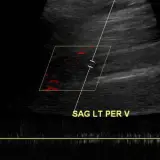

Ultrasound

75 cases Covering OB/GYN, GI/GU, and more